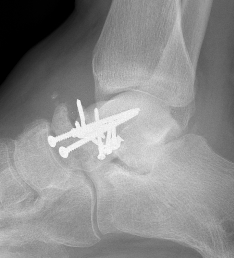

BlairblairAnkle Blair Fusion LateralAnkle Blair Fusion AP